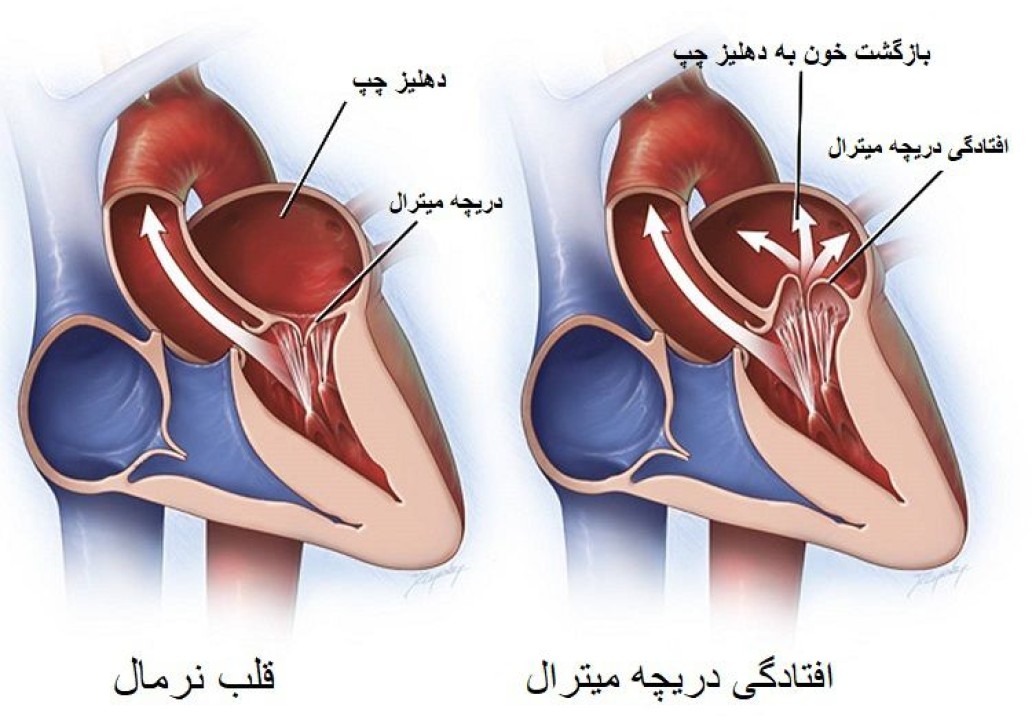

به گزارش نبض نگار: دریچه میترال دریچه ای است که اجازه می دهد خون از یک حفره قلب، دهلیز چپ، به سمت دیگری به نام بطن چپ جریان یابد. در افتادگی دریچه میترال، بخشی از دریچه میترال به طور شل به سمت عقب به داخل محفظه ای به نام دهلیز چپ می لغزد. این زمانی اتفاق می افتد که عضله اصلی قلب، به نام بطن چپ، در طول هر ضربان قلب منقبض می شود. افتادگی دریچه میترال با تنگی دریچه میترال متفاوت است. در تنگی دریچه میترال، دریچه میترال سفت و منقبض است.

در افتادگی دریچه میترال، دریچه به دلیل اندازه غیر طبیعی یا آسیب بافت های دریچه میترال به عقب می لغزد. برای اکثر افراد مبتلا به افتادگی دریچه میترال، علت ناشناخته است.

افتادگی دریچه میترال یکی از علل شایع نارسایی میترال است. این وضعیتی است که در آن مقداری خون با هر ضربان قلب از طریق دریچه میترال به سمت عقب جریان می یابد. در طول سال ها، نارسایی متوسط یا شدید میترال می تواند باعث ضعف عضله قلب شود که به عنوان نارسایی احتقانی قلب شناخته می شود.